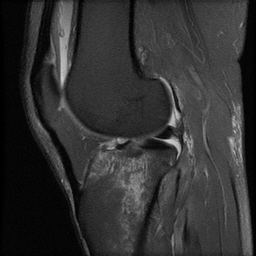

ÀÚ±â°ø¸í°Ë»ç

°æ°ñ ¿ÜÃøºÎ ¾Ð¹Ú°ñÀýÀÌ °üÂûµÊ(»çÁø 8, 9, 10)